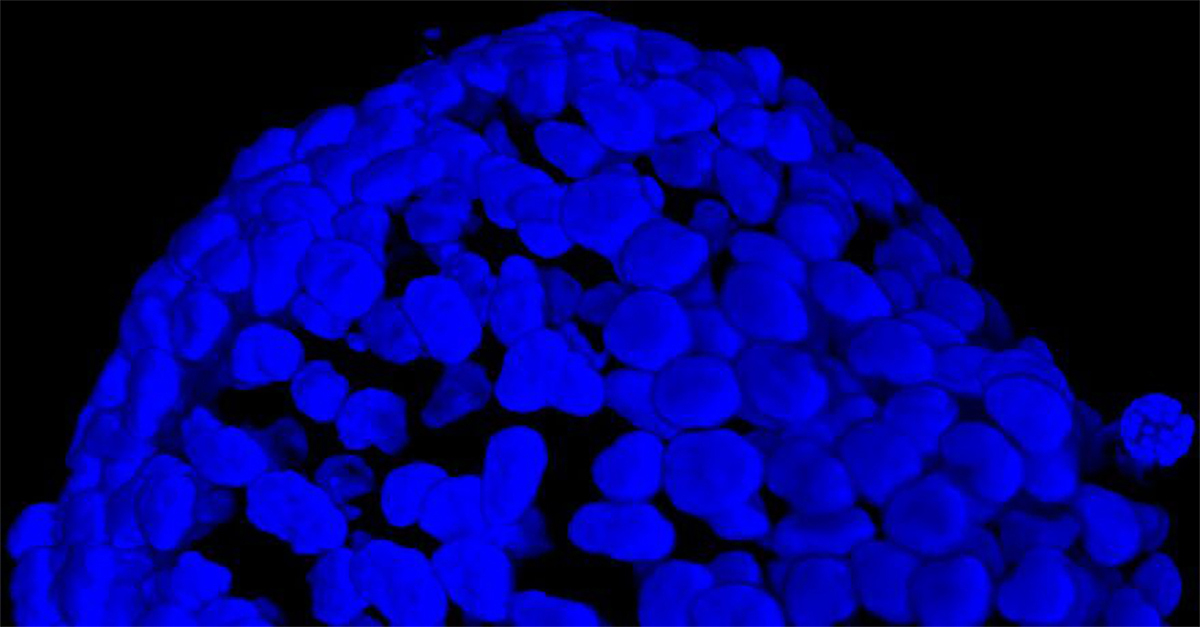

我们采用 CrestOptics X-Light V3 转盘共聚焦结合 Prime BSI 相机(Photometrics,像素尺寸 6.5 um)进行采集。我们比较了使用 20 倍空气物镜(CFI Plan Apo Lambda,尼康,0.7 NA 和 1mm WD)和 25 倍硅油物镜(CFI Plan Apo Lambda S,尼康,1.05 NA 和 0.55 mm WD)进行的采集。在图 A 中,我们展示了从总共 150 um 的 Z 堆栈中获得的最大强度投影 (MIP) 图像;特别是,使用 20 倍空气物镜和 25 倍硅油物镜获得了相同的球体。图 B 显示了使用两种物镜获得的 3D 球体同一区域的放大。

图 A:使用 20 倍空气物镜(顶部)和 25 倍硅油物镜(底部)获得的肿瘤球体 Z 堆栈的最大密度投影 (MIP)。活细胞用钙黄绿素(绿色)标记,死细胞用 PI(红色)标记。细胞核用 Hoechst(蓝色)染色。比例尺:100 um。这些图像是使用 CrestOptics X-Light V3 转盘获取的。